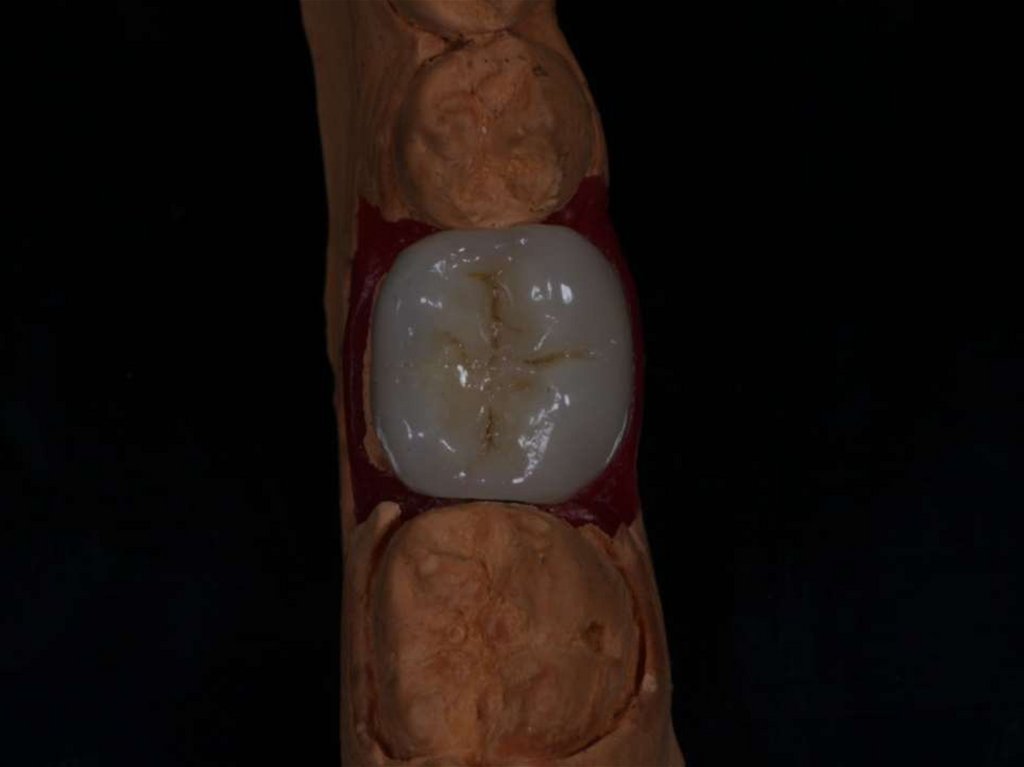

Лечение корневых каналов